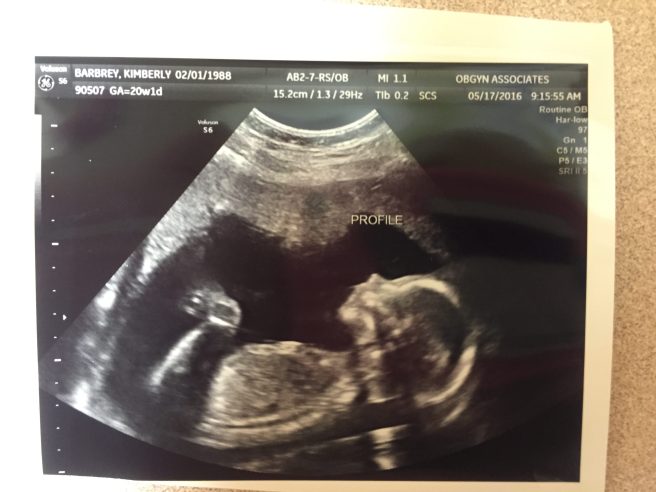

Then it was the time for our US ultrasound. I went in to the ultrasound somewhat confident, after all we pointed at something! It took the ultrasound tech not even 2 minutes to blow my confidence. She said, “they told you it was a boy? Well I am not that far into this, but I am pretty sure it is a girl.” What?! A girl. My mind was blown. We are at 2-2, my mom was with me and we laughed so hard. The tech told me things can be swollen and made to look like anything. She assured me it is not uncommon for someone like Chase and myself to miss point at something.

SO Ladies and Gentlemen meet our little girl, Piper Eleanor! Due October 3rd.